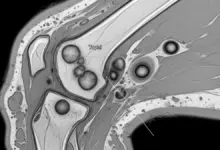

- Ultrassom: identifica cristais na cartilagem e derrame articular.

- Ressonância magnética: útil para avaliar sinovite, lesões associadas e artrose acelerada.